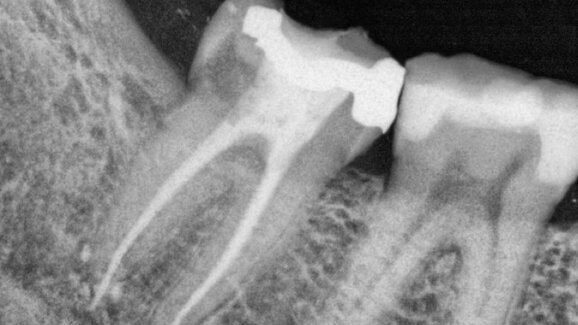

RTG snímek situace před ošetřením (obr. 1), zaslaný pacientovým zubním lékařem, ukazoval na dobře provedené ošetření kořenového kanálku, které nevysvětlovalo klinické projevy, ale při pohledu zblízka na apikální část bylo možné vypozorovat, že se materiál kořenové výplně dostal k blízkosti mandibulárního kanálu. Bylo nutné ošetření okamžitě opakovat. Bohužel byl použit plastický nosič Thermafil (DENTSPLY), který zasahoval do kanálu, čímž vznikl zánět iritující nerv. Materiál Thermafil byl z kořenových kanálků odstraněn – což nikdy není snadné – pomocí kořenových nástrojů K3XF (SybronEndo, obr. 2) a bez použití jakéhokoli rozpouštědla, aby se zabránilo dalšímu poškození nervu v případě prosáknutí. Mikromotor Elements Adaptive Motor (Kerr Endodontics, obr. 3) jsem nastavil na režim K3XF a jako první použil nástroj 25.06 v části gutaperči změkčené pomocí cpátka System B. Byl jsem velice opatrný, abych nevtlačil nosič více do nervu, a zároveň abych plastový nosič nepoškodil a nepřišel o jeho úchop. Druhým použitým kořenovým nástrojem byl 25.04 K3XF, kterým jsem odstranil další gutaperču a uvolnil nosič.

Ve druhém klinickém případě se pacient dostavil do ordinace s problémem při kousání na molár, s píštělí na bukální straně alveolu v místě dolního prvního moláru. RTG snímek před ošetřením ukázal přijatelné ošetření kořenového kanálku provedené v souladu s doporučeními (obr. 12).

Při podrobném prostudování RTG snímků bylo ale zřetelně vidět, že je něco špatně v apikální oblasti meziálních kanálků. Bližší pohled indikoval nějaký druh patologie v koronální části distálního kanálku a možnou cervikální resorpci nebo vnitřní resorpci, která by mohla vysvětlovat píštěl v této oblasti.